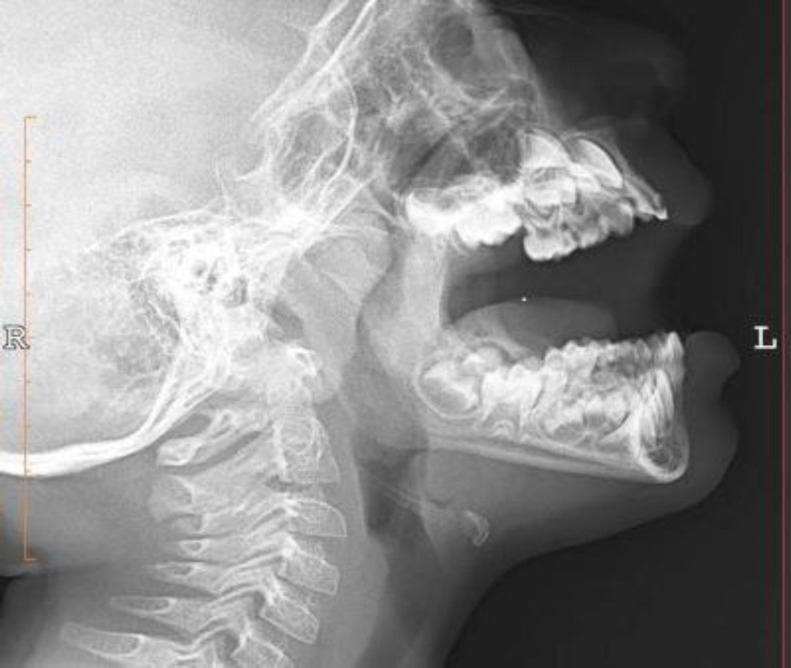

Materials and methods: The study included children aged 5 to 7 who presented with obstructive symptoms and confirmed severe adenoid hypertrophy in lateral neck radiography. Standard lateral photography was taken. The Nasofacial and Nasomental angles, and upper and lower lip positions and their distance behind the Ricketts line, were measured and compared with the normal control group.

Results: This study included 54 children with severe adenoid hypertrophy and 66 normal children. Facial angles were not significantly different between the two groups, but the mean horizontal position of the upper and lower lip in children with adenoid hypertrophy was significantly lower than in the control group (P value = 0.05). The lips were too close to the Ricketts line compared with the control group.